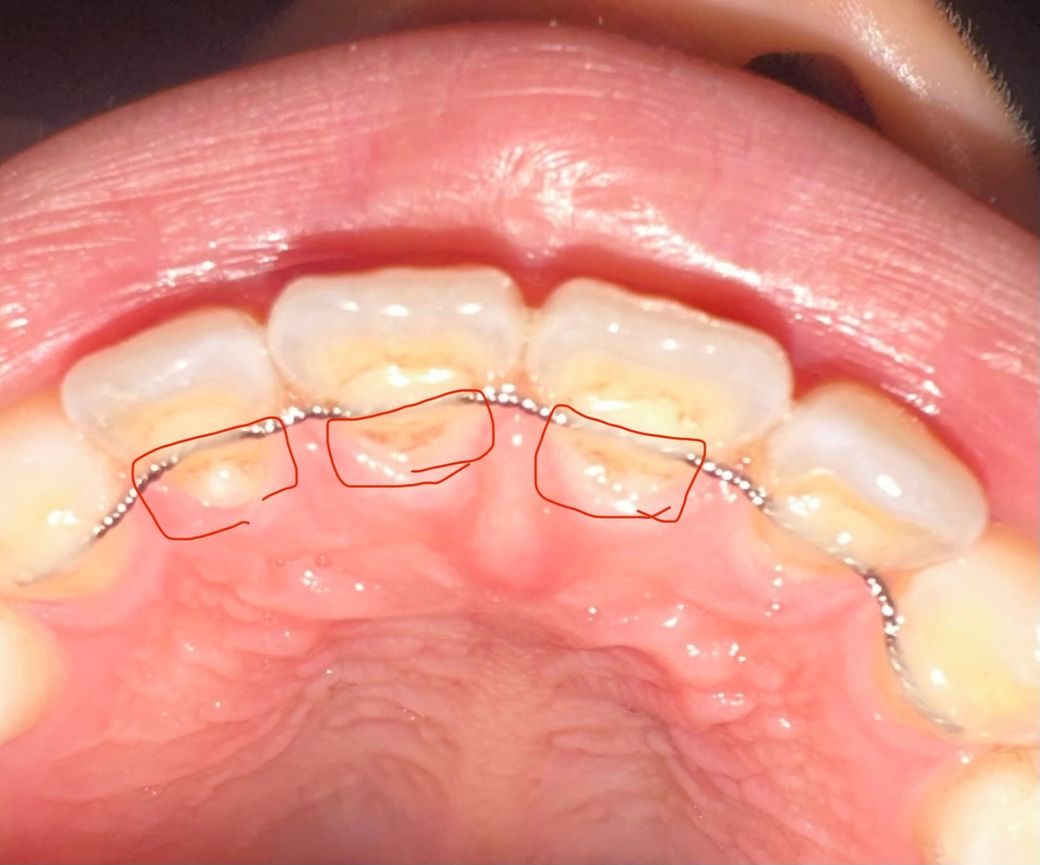

유지장치 붙은 앞니쪽에 검은게 보여요

양치하다 보니까 유지장치 붙은 앞니쪽에 검은게 보여요.

치석제거는 2개월 전에 했는데 이게 뭘까요??

아랫니는 없고 윗니에만 있어요ㅠ

유지장치를 붙혀 놓은 레진이 시간이 지나면서 착색이 된거 같습니다. 스켈링을 하면 제거가 될것같습니다.

치석일 수도 있고 레진이 착색된 것일 수도 있습니다. 그다지 문제가 될 것 같지는 않습니다.

치아 또는 유지장치 붙여둔 재료의 변색, 착색으로 보입니다 한번의 스케일링으로 완전히 제거안될 수도 있습니다

커피, 차, 초콜렛 등과 같은 색인 강한 음식이 유지장치에 남아착색이 된 것으로 보입니다. 특히 흡연자는 니코틴과 타르 성분이 유지장치 주변에 쌓여 검게 변색될수 있습니다.

치과에서 폴리싱을 받는 것이 도움이 됩니다.